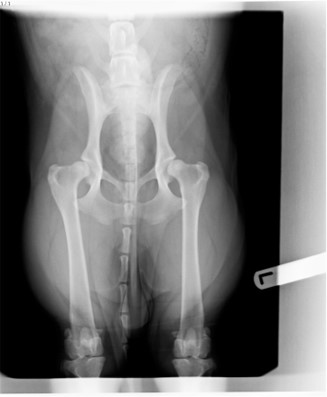

We expected our first post-operation physiotherapy appointment at the beginning of August 2022 to be a straightforward planning meeting, to discuss the progress with Sam’s front right leg, and plan when to start physiotherapy. In what was to be a regular routine, the patient, Sam, was walked slowly along the pavement outside the practice. “What about that hip?” says the Physio. “What about the hip? Which hip?” we reply. “Did the vet not spot that weakness in the left hip? You need that hip to be x-rayed”.

This was not what we wanted to hear, but it is a sub plot in the main elbow dysplasia theme and so dealt with in a paragraph. Both hips were eventually x-rayed, and “mild” hip dysplasia diagnosed, a condition unlikely to cause major problems if Sam’s weight is controlled, and hip muscles toned by physiotherapy. The hips and back muscles were included in the elbow-related physiotherapy anyway since the weak right foreleg had caused an imbalance of muscle strength on the back legs. We knew none of this at the time of this initial assessment by the physiotherapist, and it was a body blow to discover yet another problem with Sam’s health, albeit one that turned out to be of minor significance.

“Mild” hip dysplasia is my term. The physiotherapist was concerned about the condition, but the vet felt that the condition is unlikely to cause problems. I suspect that hips either suffer from hip dysplasia, or they don’t, but in Sam’s case the symptoms are not sufficiently severe to have been diagnosed had we not had physiotherapy for elbow dysplasia, or at least that is the case at two years old.